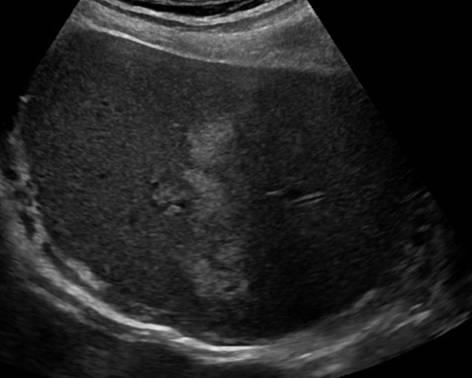

Gan nhiễm mỡ - Ảnh 4

Gan nhiễm mỡ

» Thông tin: Nam giới – 42 tuổi.

» Lâm sàng: Kiểm tra sức khỏe.